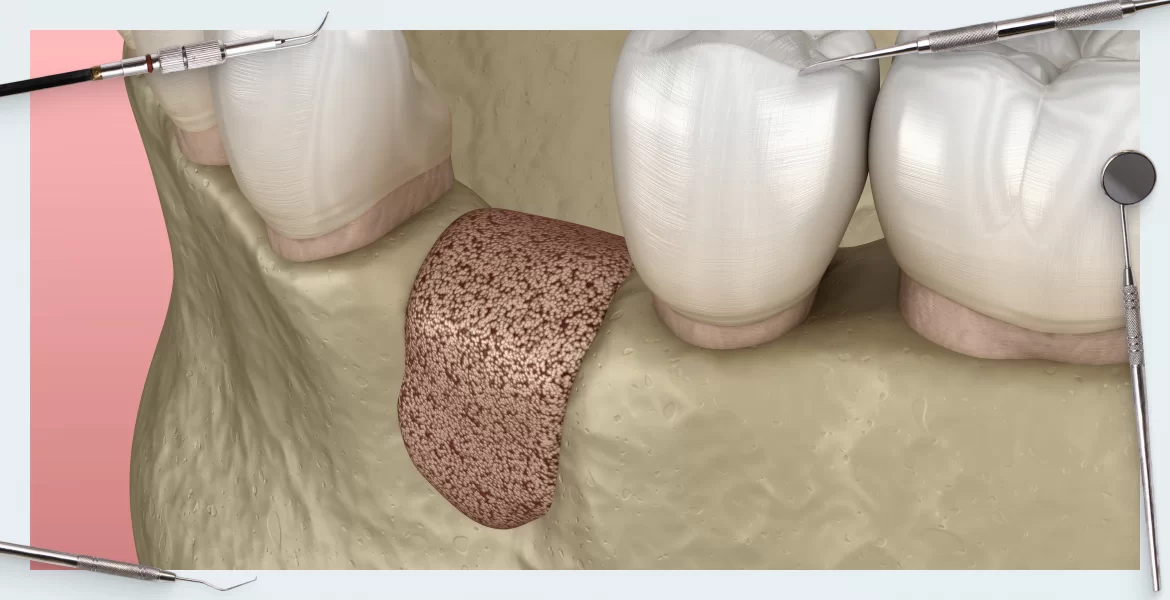

Bone regeneration and augmentation

A procedure that restores lost bone in the jaw, promoting the growth of new bone to support dental implants and improve overall oral health and stability.